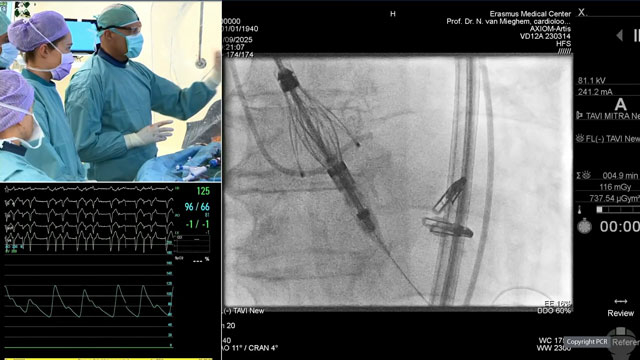

TAVI - LIVE case

18 Nov 2025 – From PCR London Valves 2025

This educational session presents a live TAVI case from St. Thomas' Hospital in London, providing detailed insights into patient presentation, imaging analysis, operator strategy, and device selection. It includes a live procedural demonstration complemented by a recorded case from Erasmus University Medical Center in Rotterdam, offering...

TAVI: LIVE Educational Case from St. Thomas' Hospital - London, UK